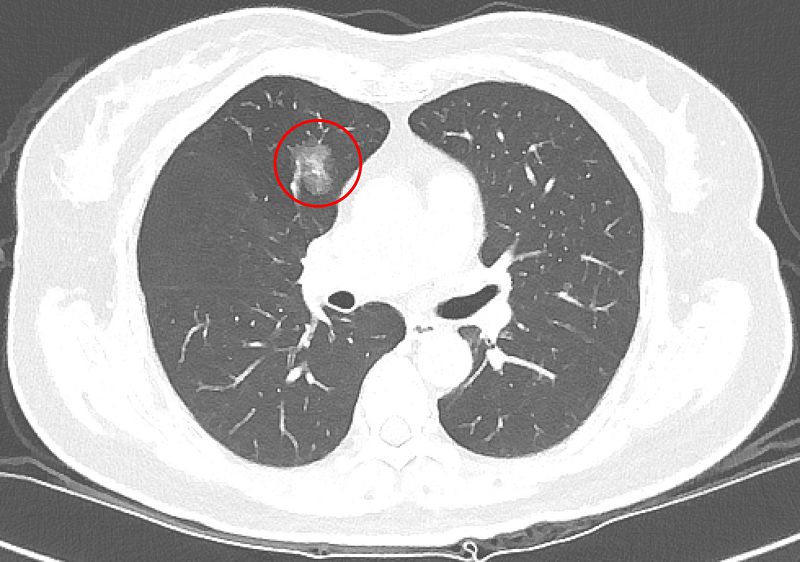

有鑑於篩檢發現的小型肺結節在診斷與後續處置上仍有不少挑戰,吳智偉醫師回溯分析台北慈濟醫院2013年至2018年間共6997名LDCT篩檢者資料,並追蹤至2023年,探討篩檢發現之肺腫瘤的生長模式、病理診斷、診斷時程及電腦斷層導引切片的準確性。研究結果顯示,接受手術或切片的腫瘤中,約有三分之二為惡性腫瘤,並以肺腺癌最為常見;而其餘三分之一的良性病理發現則是以纖維化和炭粒沉積最常見。吳智偉醫師說明,纖維化通常是肺部過去曾受感染或發炎後留下的疤痕,炭粒沉積則是空氣中的污染微粒被吸入肺部後堆積形成的結節。這兩類良性病灶之所以難以分辨,在於影像上與早期肺癌相似,因此即使經過多重評估,目前的醫學仍難以僅憑影像,準確區分良性或惡性。此外,約有13%的良性腫瘤,在追蹤的過程中以新發生的病灶(de novo)的形式被發現,讓影像的初期判斷更加艱難。

以許女士為例,沒有抽菸習慣,也沒有肺癌家族史,卻在64歲健康檢查時,從低劑量電腦斷層(LDCT)檢查中發現1.2公分的肺部結節,之後持續在胸腔內科門診追蹤。7年後,許女士71歲時,結節增大至1.4公分,因為擔憂,她與醫師討論後轉至胸腔外科手術,病理結果確診為第一期肺腺癌。由於屬早期肺癌,術後不需化療,追蹤至今恢復良好,無併發症。對此,吳智偉醫師說明,許多肺部結節通常需要追蹤很長的時間,才會有些微變化(一年約長大0.1cm),臨床上會根據變化的型態進一步評斷處置方式。